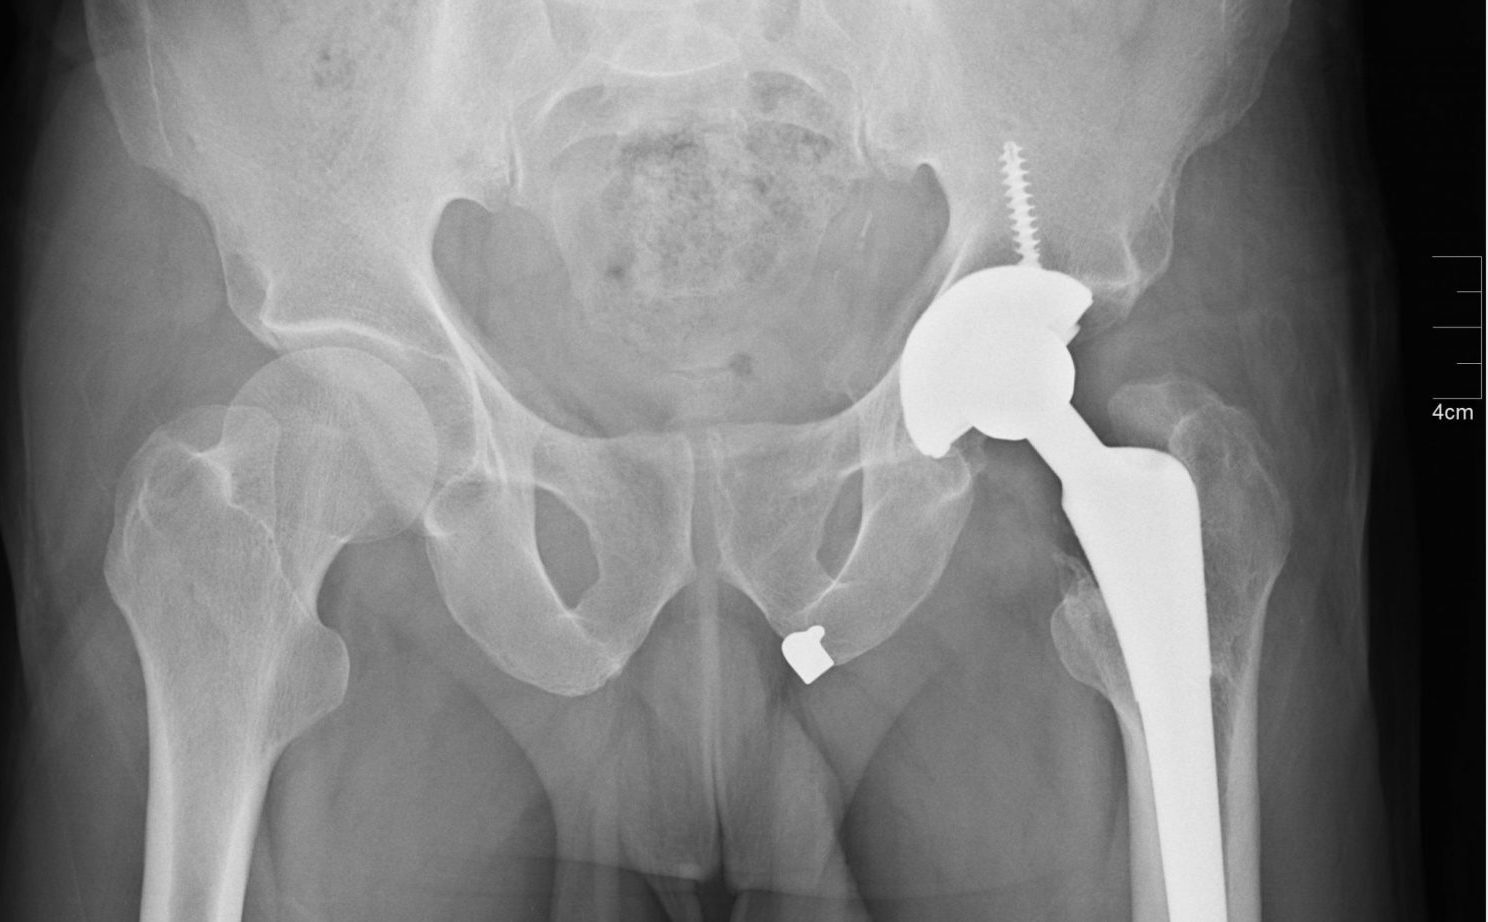

(PDF) Antibiotic prophylaxis in total hip arthroplasty Effects of Antibiotic Prophylaxis Hip Replacement Colonoscopy recent american academy of orthopaedic surgeons clinical practice guidelines (2019) have recommended the. the value of antibiotic prophylaxis for gastrointestinal (gi) procedures has been debated for many. the document specifically states that for esophageal and gastroduodenal procedures, cefazolin 1 to 2 g intravenously may be. the role of antibiotic prophylaxis is to reduce the possibility of. Antibiotic Prophylaxis Hip Replacement Colonoscopy.